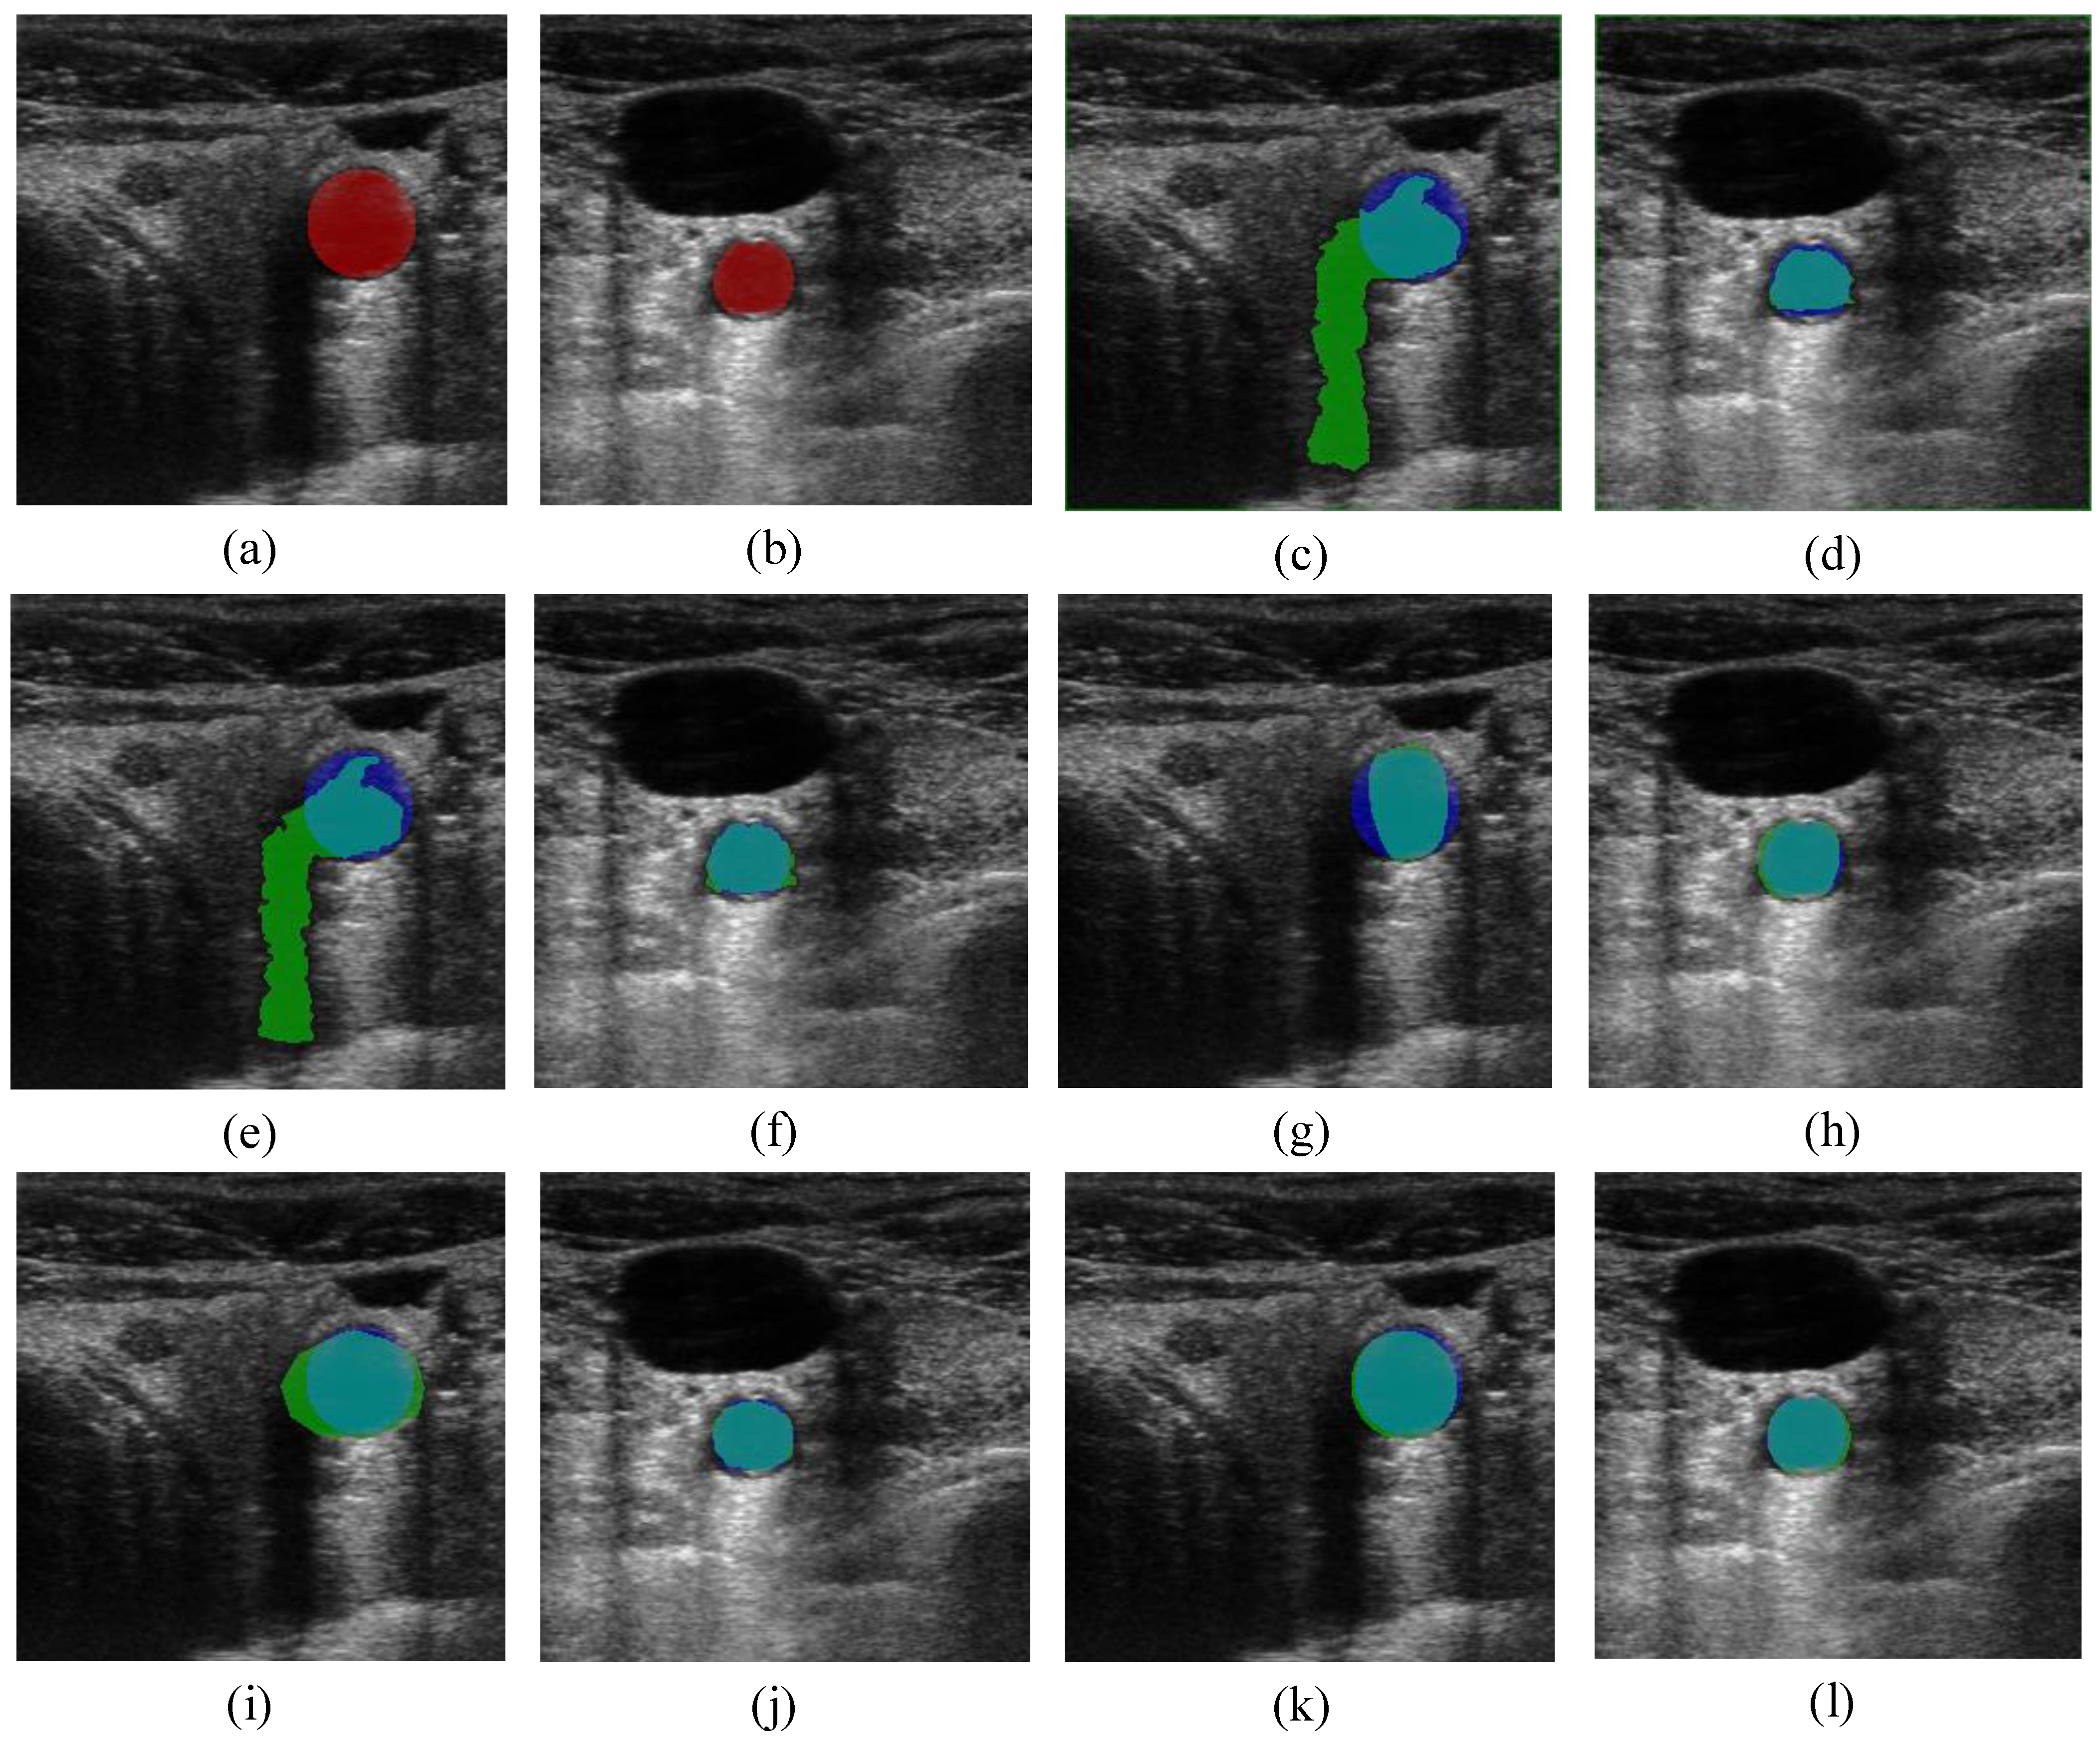

and  the random vectors in the evaluated generation. Figure 8 shows the obtained segmentation results with different mutation operators. To perform this test, the experiment has been repeated 10 times (per each operator) and the mean of the obtained results has been computed. It can be observed that the best mutation operation can have an impact of about 3% in precision and almost 1% in the F-measure with respect to the worst case.

the random vectors in the evaluated generation. Figure 8 shows the obtained segmentation results with different mutation operators. To perform this test, the experiment has been repeated 10 times (per each operator) and the mean of the obtained results has been computed. It can be observed that the best mutation operation can have an impact of about 3% in precision and almost 1% in the F-measure with respect to the worst case.